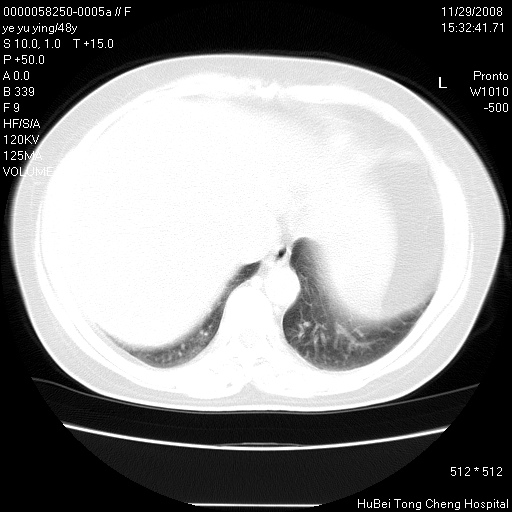

以下是引用zsl6918在2008-11-29 21:47:00的发言:[br]恶性肿瘤病史,转移瘤首先考虑。脂肪肝,胆囊结石。

以下是引用huenhao在2008-11-29 22:11:00的发言:[br]脂肪肝,胆囊结石。左肺病灶建议定期复查。

以下是引用liuyue在2008-11-30 5:44:00的发言:[br]1.左肺病变,首先考虑感染性病变,转移待排;建议治疗后复查。[br]2.肝脏密度普遍减低,考虑与化疗有关。[br]3.胆囊结石.